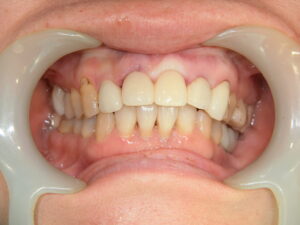

症例写真

before

after1

after2

| 施術名 | 抜歯即時荷重 |

| 施術の説明 | 歯を抜歯してすぐにインプラントを埋入し、そのインプラントに仮歯を装着する治療方法 |

| 施術の副作用 | 噛んでしまうことで骨とインプラントの結合が不十分になる可能性があり、インプラントの安定性に問題が生じることがあります。十分な検討と適切なアフターケアーが必要です。 |

| 施術の価格 | 495,000円(税込)×2 ポンティック 110,000円(税込) ※2本でブリッジ+ポンティックのケース |